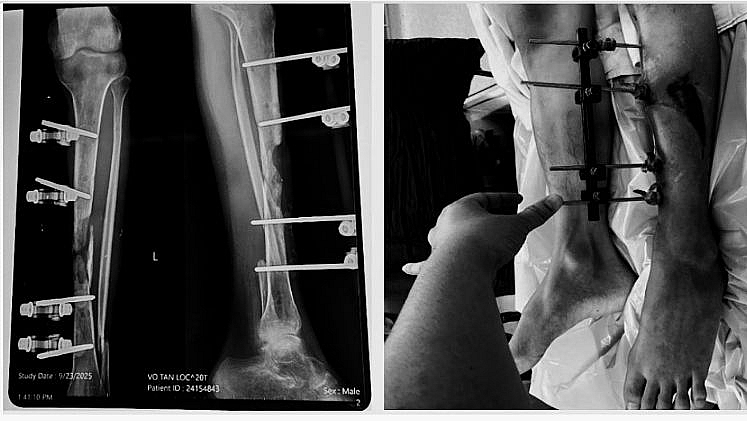

Bệnh nhân nam V.T.L, sinh năm 2005, tiền sử gãy hở 2 xương cẳng chân trái đã được phẫu thuật đặt khung cố định ngoài, sau đó diễn biến viêm xương tủy xương điều trị nhiều đợt đến khi ổn định. Ngày 23/09, bệnh nhân nhập viện vào khoa Bỏng và Vi phẫu tạo hình, Viện Chấn thương chỉnh hình trong tình trạng: Sẹo mổ cũ vùng trước xương chày xơ dính, còn khung cố định ngoài, khuyết xương chày khoảng 8 cm, gãy cũ xương mác trái, chân trái ngắn hơn chân phải khoảng 2 cm, không còn biểu hiện viêm hay nhiễm trùng.

Trước khi phẫu thuật khuyết hổng xương chày do viêm xương tủy

Sau 14 ngày phẫu thuật, vạt da hồng hào, siêu âm tại vùng nhận vạt mạch máu lưu thông tốt, đảm bảo vạt sống 100%, hình ảnh X-quang cho thấy xương thẳng trục, chiều dài 2 chân bằng nhau. Bệnh nhân hồi phục tốt, sinh hoạt bình thường, không có biến chứng sau mổ.